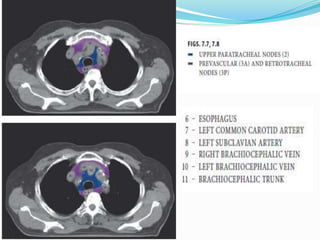

The International Association for the

 14 LN stations reorganized into 7 zones

 Supraclavicular zone

 Upper zone

 AP zone

 Subcarinal zone

 Lower zone

 Hilar zone

 Peripheral zone

Upper zone

AP zone

Subcarinal zone

Lower zone

Hilar zone

Lymph nodal stations in ca lung